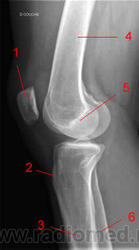

Область коленного сустава.

1, Боковой (латральный) мыщелок бедренной кости.

2, Бедренная кость.

3, Надколенник.

4, Медиальный мыщелок бедренной кости.

5, Межмыщелковое возвышение.

6, Б/берцовая кость.

7, М/берцовая кость.